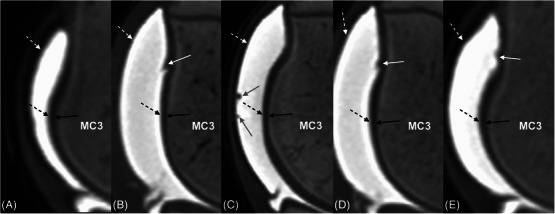

Articular cartilage can be directly imaged using ultrasonography. The fetlock is a common site of osteochondrosis, with the sagittal ridge of the third metacarpal bone most commonly affected. In osteochondrosis, cartilage thickening may be an initial finding. This postmortem study investigated the ability of ultrasonography to accurately measure the dorsodistal articular cartilage of the third metacarpal bone in young horses, compared to computed tomographic arthrography (CTA) and histological measurements. A total of 33 metacarpophalangeal joints from 18 horses between the ages of 12 days and 10 months old were imaged ultrasonographically and with CTA and sectioned and measured using histology. Imaging measurements were made by two observers. Despite overall weak agreement between ultrasonography and histology, the best agreement was at the distal aspect of the sagittal ridge of the third metacarpal bone. Interobserver agreement at this site was also moderate. CTA showed poor agreement overall with histology. Cartilage thickness decreased with age on ultrasonography, CTA, and histology. In conclusion, ultrasonography is a more accurate imaging modality than CTA in the assessment of cartilage in young horses.